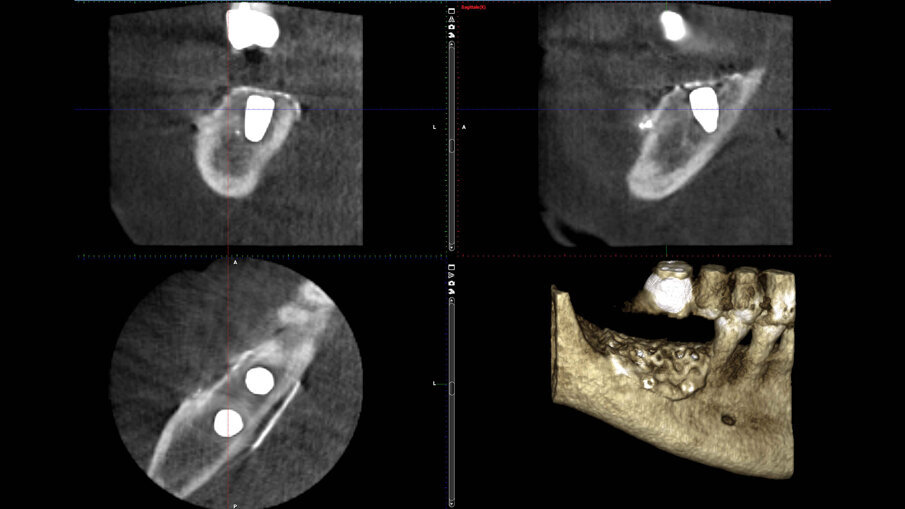

Nell’area edentula mandibolare, erano visibili un deficit osseo orizzontale e verticale che necessitava di una rigenerazione ossea ma che avrebbe permesso l’inserimento contestuale di impianti endossei (Figg. 1a-1c). La paziente, dopo valutazione delle alternative terapeutiche, sceglieva di eseguire una rigenerazione ossea protetta con l’utilizzo di una griglia in titanio customizzata contestualmente all’inserimento implantare. In una seduta successiva, venivano quindi rilevate delle impronte e veniva costruita una ceratura diagnostica con denti di dimensioni e posizione ideale per ottenere corretti rapporti intra- e inter-arcata e, successivamente, una dima diagnostico-radiologica con reperi radio-opachi, utilizzata per l’esecuzione di una CBCT.

Figg. 1a-1c_Foto clinica e sezioni di CBCT iniziali in cui si evidenzia edentulia distale all’elemento 4.5 con atrofia tridimensionale.